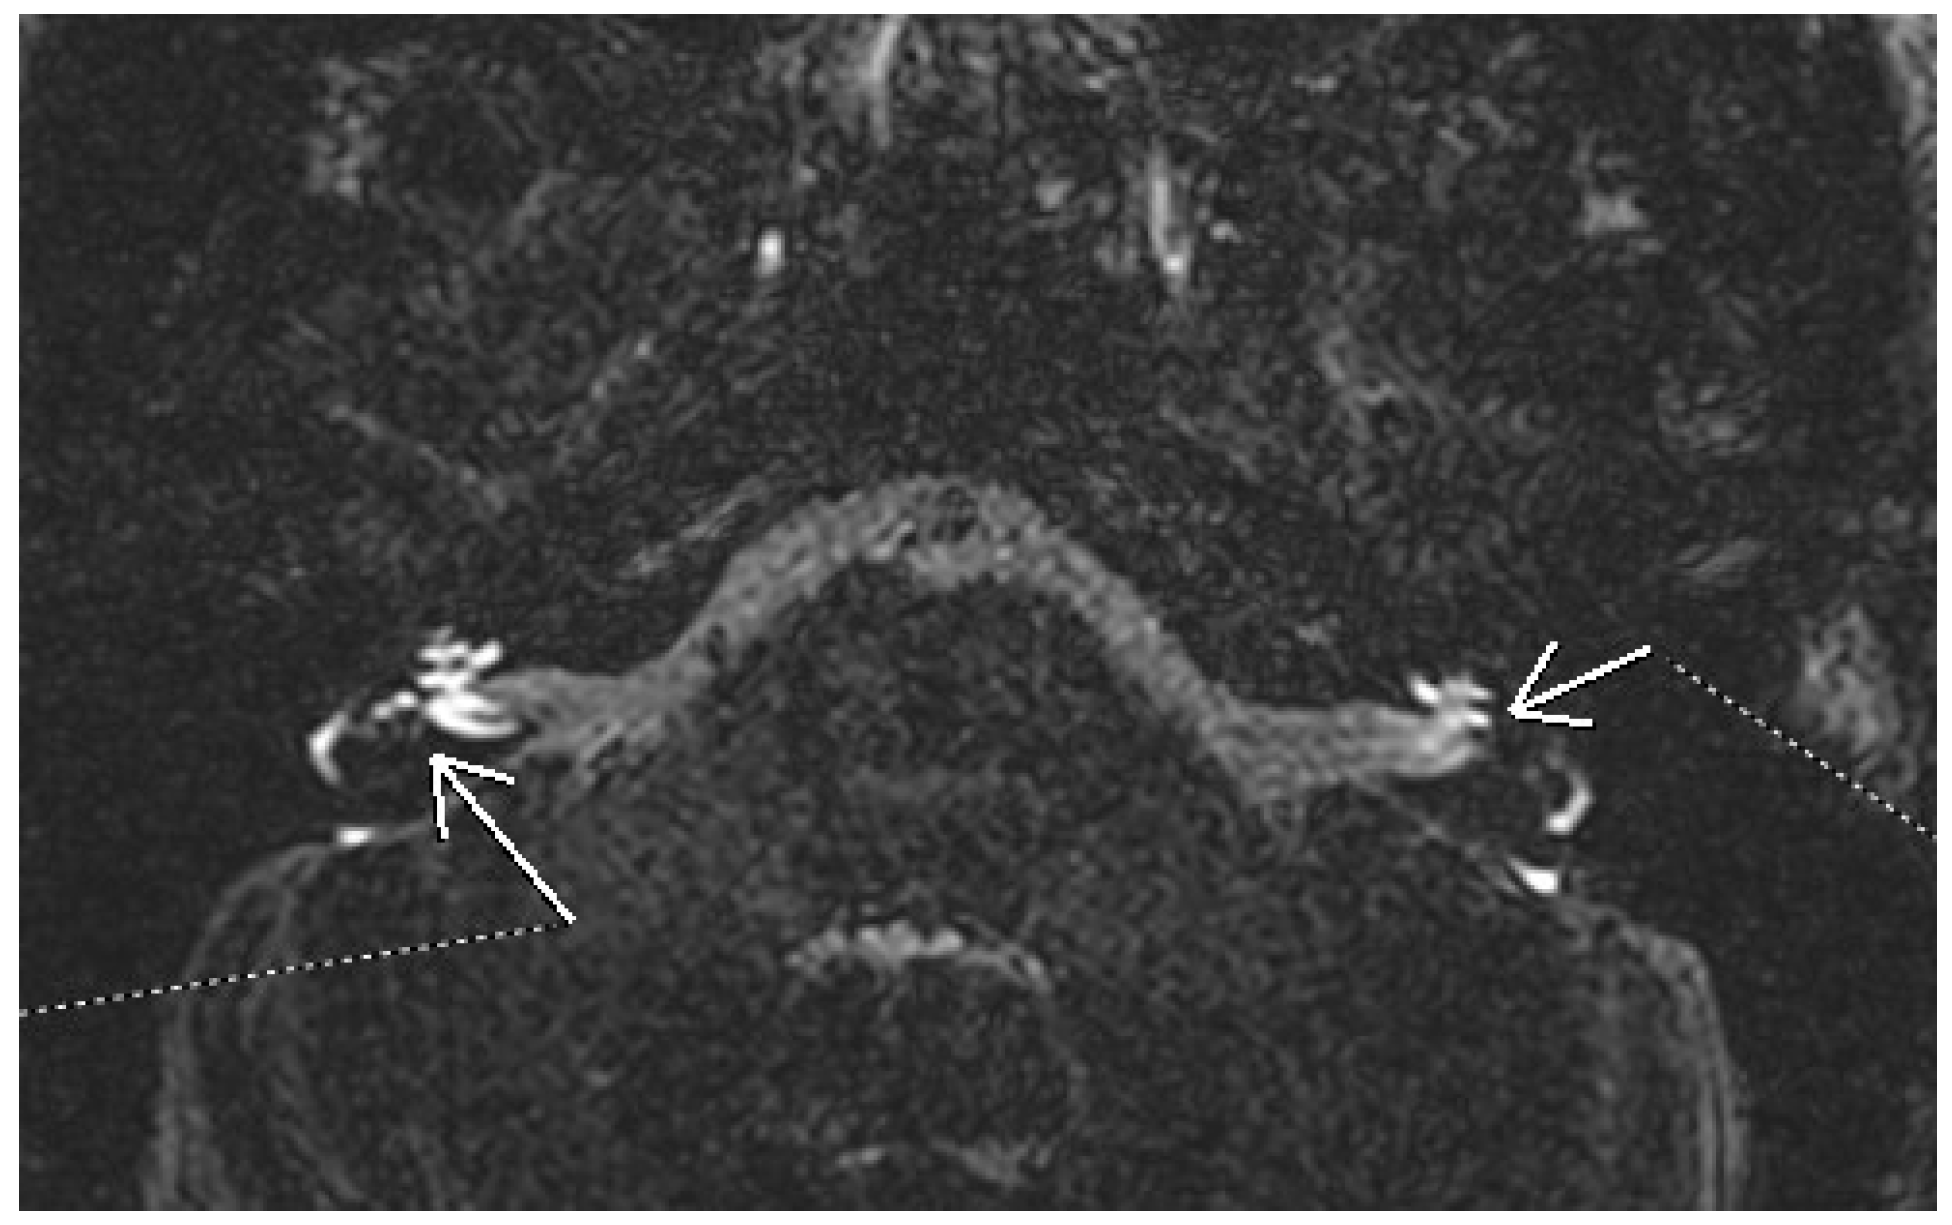

- Farhat, R.; Abu Awad, A.; Abu Shaheen, W.; Alwily, D.; Avraham, Y.; Najjar, R.; Merchavy, S.; Massoud, S. The “Vestibular Eye Sign”—“VES”: A new radiological sign of vestibular neuronitis can help to determine the affected vestibule and support the diagnosis. J. Neurol. 2023, 270, 4360–4367. [Google Scholar] [CrossRef]

- Eliezer, M.; Maquet, C.; Horion, J.; Gillibert, A.; Toupet, M.; Bolognini, B.; Magne, N.; Kahn, L.; Hautefort, C.; Attyé, A. Detection of intralabyrinthine abnormalities using post-contrast delayed 3D-FLAIR MRI sequences in patients with acute vestibular syndrome. Eur. Radiol. 2019, 29, 2760–2769. [Google Scholar] [CrossRef]

- Byun, H.; Chung, J.H.; Lee, S.H.; Park, C.W.; Park, D.W.; Kim, T.Y. Clinical value of 4-hour delayed gadolinium-Enhanced 3D FLAIR MR Images in Acute Vestibular Neuritis. Laryngoscope 2018, 128, 1946–1951. [Google Scholar] [CrossRef] [PubMed]